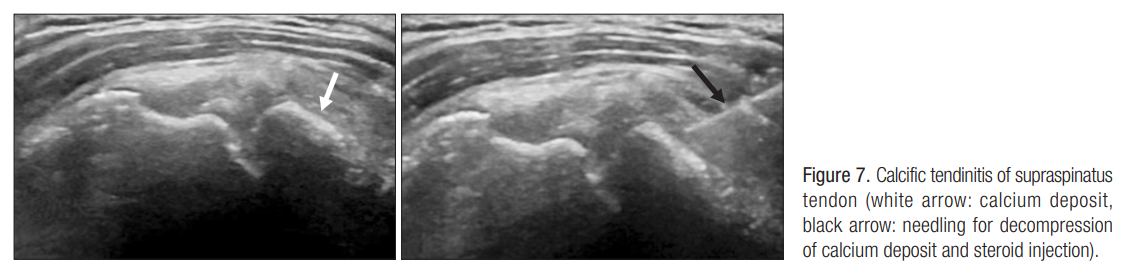

4. 석회성 건염 주사 치료( Calcific tendinitis injection)

석회성 건염 중 30퍼센트 가량이 통증이 심한 석회화 건염

초음파의 반사가 확연하여 하얗게 보이는 부위에 21 게이지 needle을 이용해서 수차례 needling

석회의 감압을 유도한 뒤 스테로이드 주사를 시행.

(석회에 진입 시 저항이 건 진입 시와 다르다)

얇은 두께의 needle을 사용하는 경우, needle 끝이 석회에 막혀 주사액이 주입되지 않는 경우도 있어, 최소 21 게이지 이상 사용하고, 18게이지까지 사용할 수 있다.

post acoustic shadow 여부로 형성기 혹은 흡수기 상태에 대한 판단

: 형성기의 경우에는 needle 끝으로 석회를 천공시켜 석회를 감압시키고, 약물을 주입하고 다시 aspiration하는 barbotage

: 흡수기의 경우에는 barbotage 술식과 함께 인접 bursa에도 약물을 주입(inflammation이 심하므로)

-> 회전근개의 부분 손상이 동반된 경우가 많으므로, 이때 회전근개 자체에는 주입하지 않는 것이 원칙